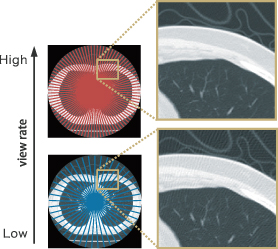

С максимальной скоростью 0,35 с/об можно сканировать не только сердце, но и другие области тела, что позволяет сохранить достаточную плотность данных на периферии. Это реализовано в высокоскоростной системе сбора данных с максимальной частотой сканирования 2880 сканов/с, разработанной специально для компьютерного томографа SCENARIA.

Алгоритм CORE

Алгоритм CORE (Cone-Beam-Reconstuction — реконструкция конического пучка) оптимизирует порядок полученных данных, используемых для реконструкции по пикселям. За счет эффективного использования всего диапазона детекторов доступным становится большее количество данных по сравнению с методом Фальдкампа. С помощью алгоритма удается уменьшить полосчатые артефакты, которые, как правило, формируются от краев ребер при сканировании с большим питчем, и двигательные артефакты, вызванные перистальтикой ЖКТ, благодаря чему получаются изображения высокого качества.